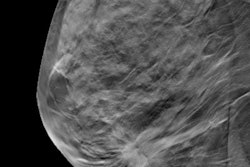

Screening with digital breast tomosynthesis (DBT) doesn't increase the use of BI-RADS category 3 -- a designation that prompts intensive follow-up and tracking for up to two years and can provoke anxiety in patients, according to a study published online July 17 in Radiology.

For the study, McDonald and colleagues included 10,728 screening digital mammography exams (taken between September 2010 and August 2011) and 15,571 screening digital mammography plus DBT exams (taken between October 2011 and February 2013). Recall rates were 10.4% for digital mammography and 8.8% for DBT plus mammography. The group also classified recall exams by finding type (calcifications, asymmetry or focal asymmetry, mass, and architectural distortion).